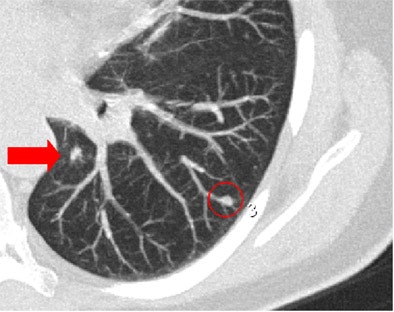

| Concurrent use of CAD in primary reading may result in less careful examination by radiologists. In one session in which CAD was being used as a concurrent reader, LungCare software marked a nodule in the periphery of the apical lower lobe of the left lung (red circle). However, two radiologists missed the centrally located nodule located on the same slice (arrow), while only one radiologist missed the same nodule when CAD was used as a second reader. Image courtesy of Dr. Florian Beyer. |